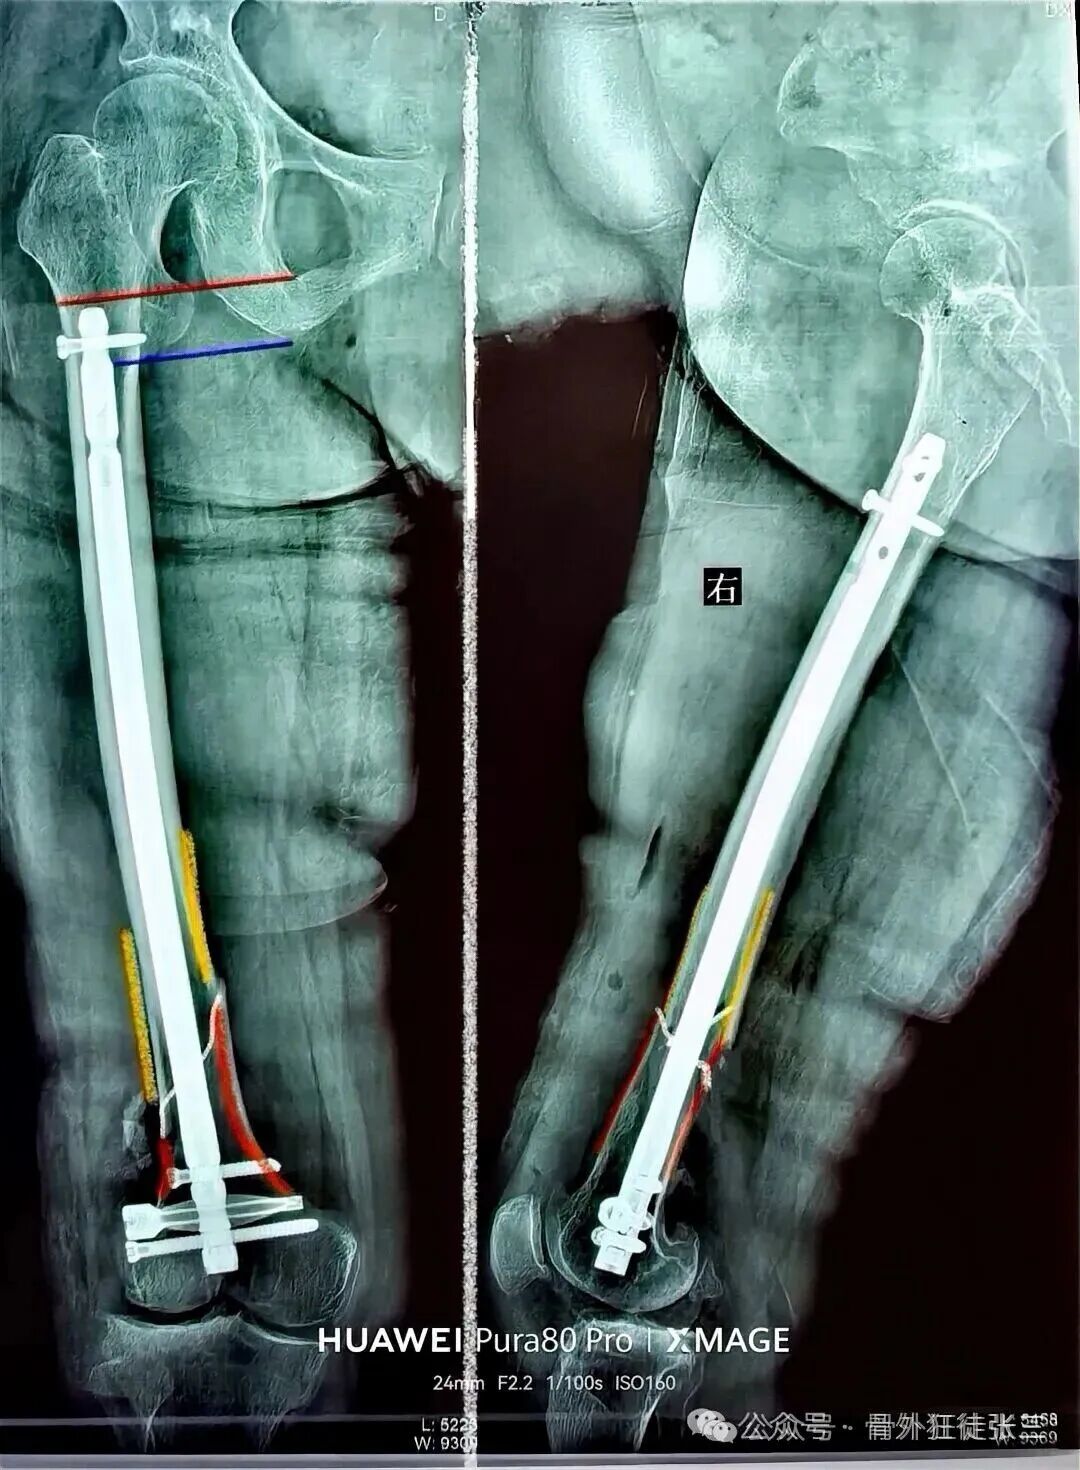

我们给予翻修

1,顺行髓内钉,头颈模式

2,全长保护,

3,最粗,够长

这样全长保护

转子下,股骨颈或者股骨远端再骨折的概率

是不是非常小

几乎不会再出现?

所以还是坚持我们的观念

股骨干骨折

能髓内钉,不钢板

能顺行,不逆行

能闭合,不切开

髓内钉,要顶天立地

够粗,够长,够坚强